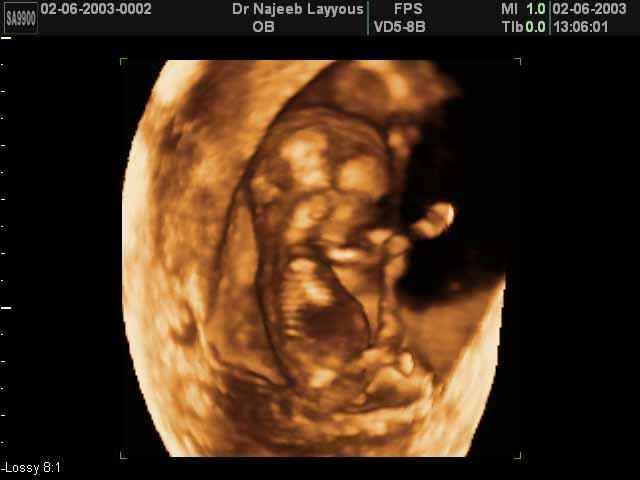

- First Trimester Ultrasound Photos

3D First Trimester Ultrasound Scan Photos ( Early Pregnancy Ultrasound Photos ) | Dr N Layyous